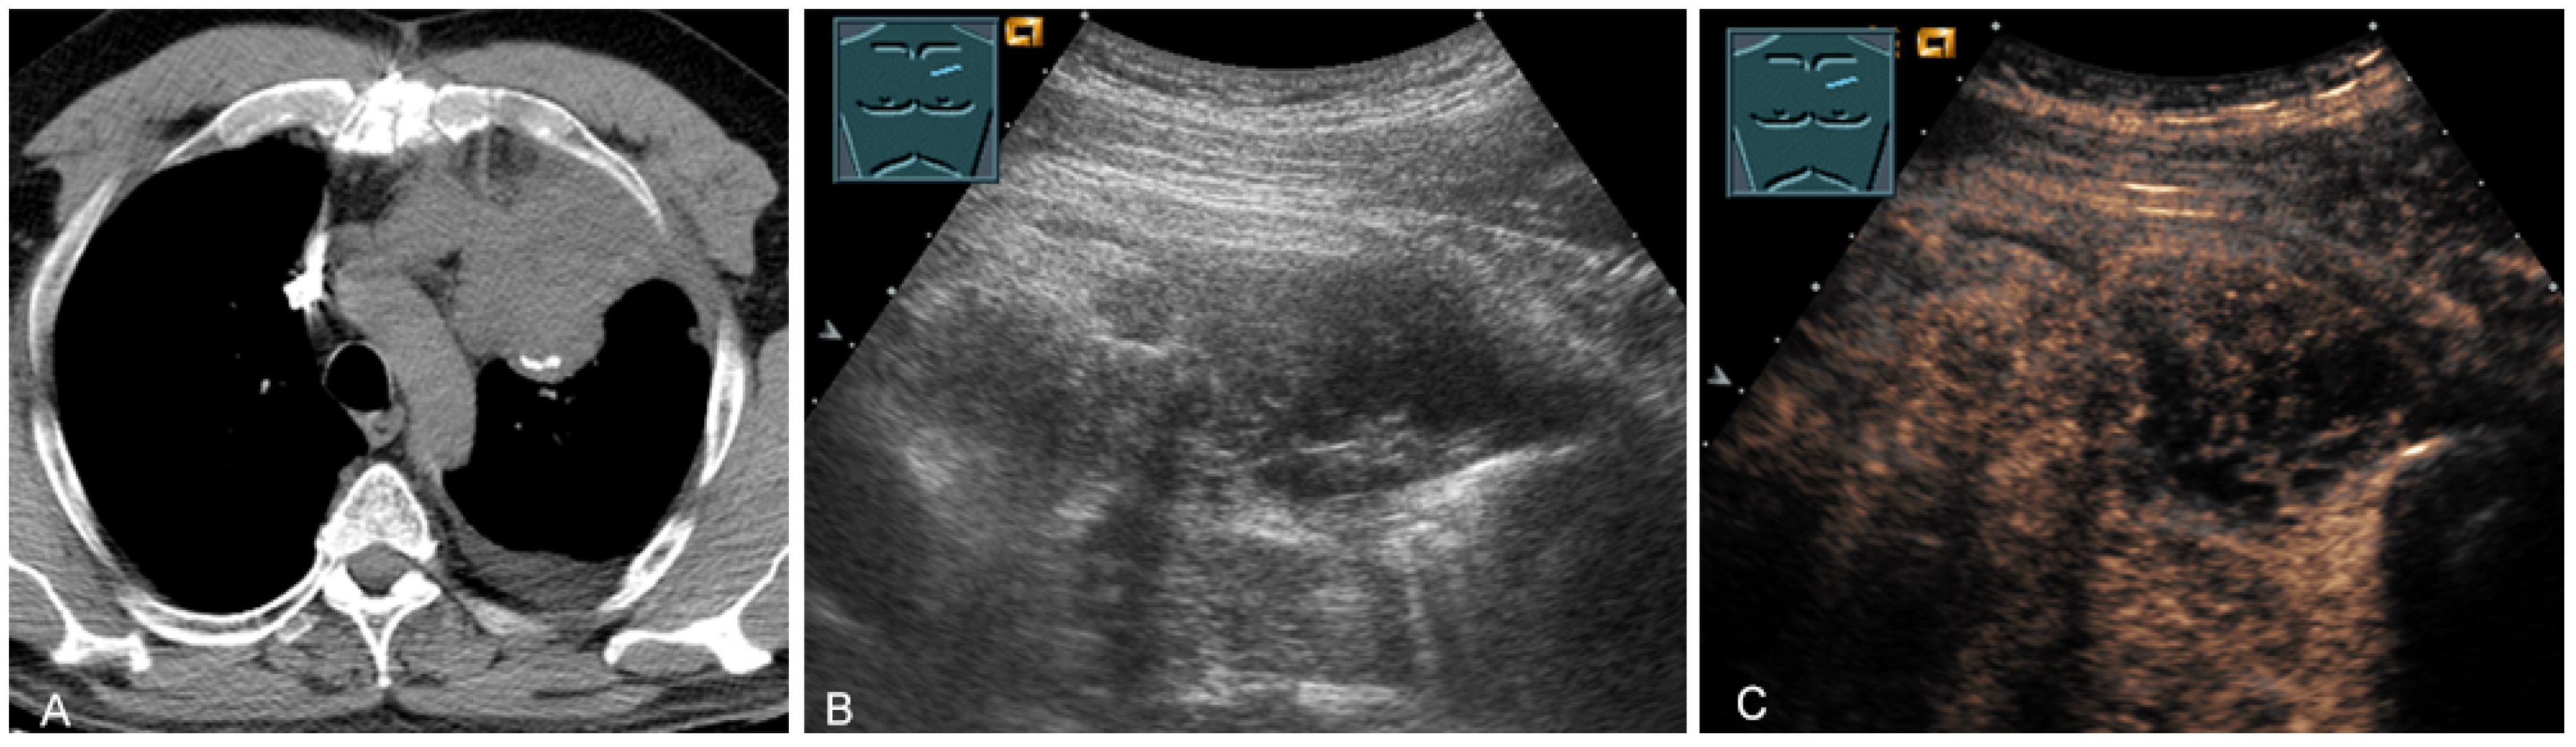

The last-mentioned entities are predominantly located in the paravertebral mediastinum. Primary malignant mediastinal masses of the prevascular mediastinum include malignant thymomas (Figure 19) or thymic carcinomas (Figure 20), Hodgkin’s disease (Figure 21), malignant non-Hodgkin’s lymphoma (Figure 22), and extragonadal germ cell tumors, including malignant teratomas (Figure 23) and seminoma [28,31,36].

Figure 19.

A patient with tumor formation in the anterior mediastinum on CT (provided by Prof. Dr. Andreas H. Mahnken, Marburg, Germany) (A), B-mode US (B), and CEUS (C), surgically confirmed as malignant thymoma stage B1.

Figure 20.

A patient with tumor formation in the anterior mediastinum on CT (provided by Prof. Dr. Andreas H. Mahnken, Marburg, Germany) (A), B-mode US (B), and CEUS (C), surgically confirmed as lymphoepithelioma-like malignant Thymoma B2.

Figure 21.

A young patient with tumor formation in the anterior mediastinum on CT (provided by Prof. Dr. Andreas H. Mahnken, Marburg, Germany) (A), B-mode US (B), and CEUS (C), confirmed by biopsy as Hodgkin’s disease.

Figure 22.

A patient with tumor formation in the anterior mediastinum on CT (provided by Prof. Dr. Andreas H. Mahnken, Marburg, Germany) (A), B-mode US (B), and CEUS (C), confirmed by biopsy as diffuse large B-cell non-Hodgkin’s lymphoma.

Figure 23.

A patient, with a history of germ cell tumor, with tumor formation in the anterior mediastinum on CT (provided by Prof. Dr. Andreas H. Mahnken, Marburg, Germany) (A), B-mode US (B), and CEUS (C), confirmed by biopsy as mediastinal metastasis of malignant teratoma.